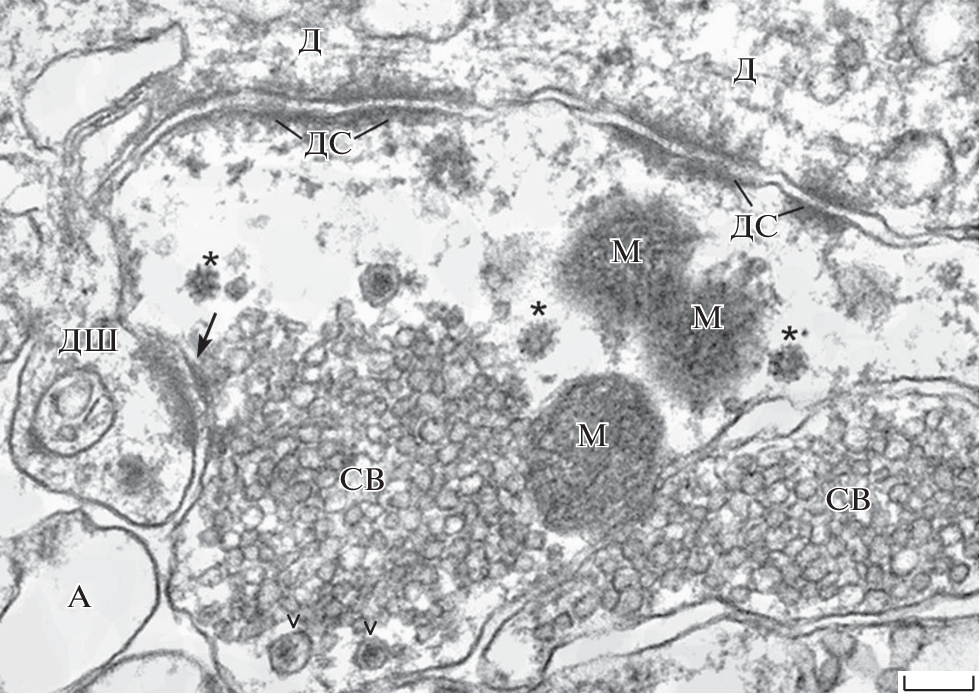

Suppression of glycolysis in the rat hippocampal formations was induced by daily intracerebroventricular injection of 2-deoxy-D-glucose for 10 days. Using electron microscopy, a disturbance of morphological interactions of axonal terminals of granular neurons with perisynaptic astrocytic processes was found. At the same time, both the determinant ultrastructural characteristics of giant synapses and two types of functional contacts (asymmetric chemical active zones with dendritic spines and symmetric adhesive junctions with dendrites) were retained. However, they showed morphological signs of a weakening of synaptic processes, which were expressed in a decrease in the number of intraterminal active zones, clustering of synaptic vesicles, and their removal from neurotransmitter release sites. Compared to the norm, an increase in the number of small mitochondria with an electron-dense matrix and the evidence of initiation of glycogen synthesis in the form of glycosomes were found in the giant terminals. The data obtained indicate that the giant synapses of the hippocampal mossy fibers are a plastic, self-correcting system that is able to function by adapting its own bioenergetic metabolism, when brain glycolysis is suppressed.